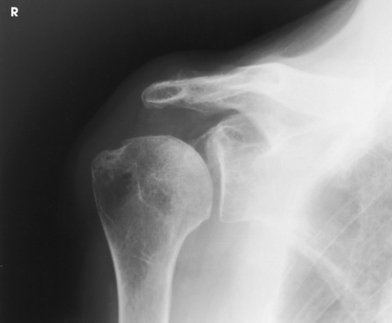

Anterior dislocations of the shoulder frequently result in posterior defects involving the posterolateral head of the humerus. Such defects, called Hill-Sachs defects,1 are often not shown using conventional radiographic positions. Hall et al.2 described the notch projection, from ideas expressed by Stryker, as being useful to show this humeral defect.

Structures shown: The resulting image shows the posterosuperior and posterolateral areas of the humeral head (Figs. 5-46 and 5-47).

Fig. 5-47 Same projection as in Fig. 5-46 in a patient with small Hill-Sachs defect (arrow).